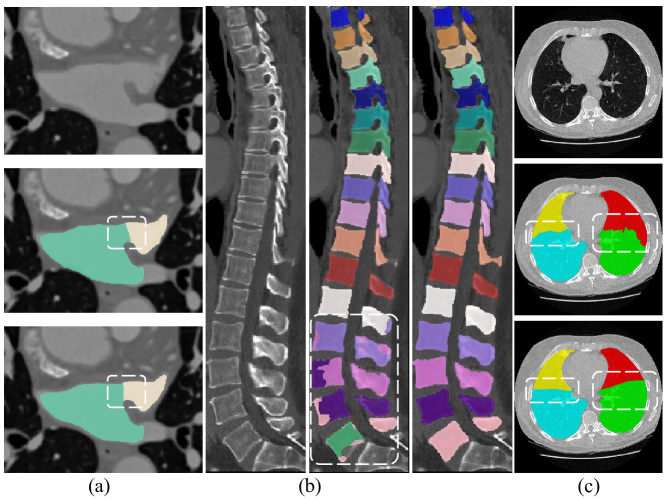

Figure 1: Three types of boundary confusion. (a) The obstacle in obtaining the unified standard for annotations of inter-class boundaries (Upper and lower annotations from junior and senior clinicians respectively). (b) Adjacent boundaries between anatomies with similar appearances but different classes. (From left to right: image/ prediction by vanilla 3D UNet/ground truth). (c) Unclear boundaries or noise near boundaries. (From top to bottom: image/ prediction by vanilla 3D UNet/ground truth). -

The obstacle in acquiring a uniform standard for annotations of inter-class boundaries due to skill variations: For some anatomical structures closely connected to each other, it is very significant but challenging to have an accurate segmentation mask of intricate interfaces between different anatomies. However, for structures like the aortic lumen and wall [16], the left atrial appendage (LAA) and left atrium (LA) [17] and so forth, there is a dilemma in achieving an identical standard for annotating boundaries between two anatomies. As illustrated in Figure 1, upper and lower annotations are carried out by junior and senior clinicians. Here a lack of uniform standards for boundary ground truths (GTs) will also introduce uncertainty to the output of neural networks [18], which finally results in the phenomenon of boundary confusion.

Adjacent boundaries between anatomies with similar appearances but different classes: if anatomies show homogeneous structures, there is likely to be segmentation inconsistency inside each anatomical structure [19]. Concretely, each anatomical structure should be labeled as a unique class. However, the same label will occur inside other anatomies with a homogeneous appearance, causing inaccurate boundary segmentation for anatomical structures. This phenomenon also belongs to the scope of boundary confusion. As shown in Figure 1, typical examples include vertebral CT images [20]. Besides, When objects are close to each other but not intersecting, models may falsely fill in the blank space between objects if no additional constraints are added to train the segmentation networks [21].